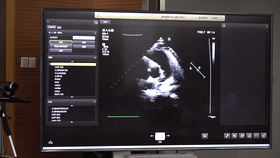

5G遠(yuǎn)程會診現(xiàn)場,西安國際醫(yī)學(xué)中心心內(nèi)科張衛(wèi)澤主任、超聲科陳姍姍主任打開4K高清顯示器,屏幕上立刻出現(xiàn)了商洛國際醫(yī)學(xué)中心的B超畫面,一位醫(yī)生正在為患者做心臟B超,隨著探頭的轉(zhuǎn)動(dòng),超聲機(jī)器上的畫面清晰可見,雖然兩家醫(yī)院相距一百多公里,但畫面流暢,沒一點(diǎn)拖沓。

“真的太棒了”張衛(wèi)澤表示,“沒有延時(shí)與卡頓,清晰的好像在一個(gè)房間內(nèi)進(jìn)行病歷討論”。陳姍姍非常興奮,直呼很震撼。她告訴筆者,“以前做遠(yuǎn)程會診,經(jīng)常遇到畫面和聲音不在一個(gè)頻道、畫面模糊等情況,遇到疑難病歷只能將影像拷下來回去研究,現(xiàn)在好了這些問題都將一次性解決?!?/span>